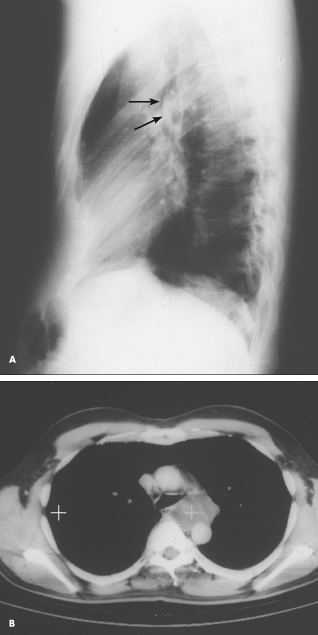

A chest roentgenogram from a 42-year-old man with asthma, primary hypoparathyroidism, and pectus excavatum showed a left suprahilar mass-like density (A, arrows). A CT scan showed this to be a cystic lesion to the left of the esophagus and posterior to the left main-stem bronchus (B, white cross). At surgery, it proved to be a 6.5 3 5.5 3 4-cm tense, tan, thin-walled unilocular esophageal foregut cyst, which was resected. The cyst contained a clear, mildly mucous fluid. The smooth inner cyst wall was approximately 1 mm thick and consisted of ciliated epithelium overlying connective tissue.

(Case, film, and scan courtesy of Drs Susan H. Allen and Terry Hoyt.)